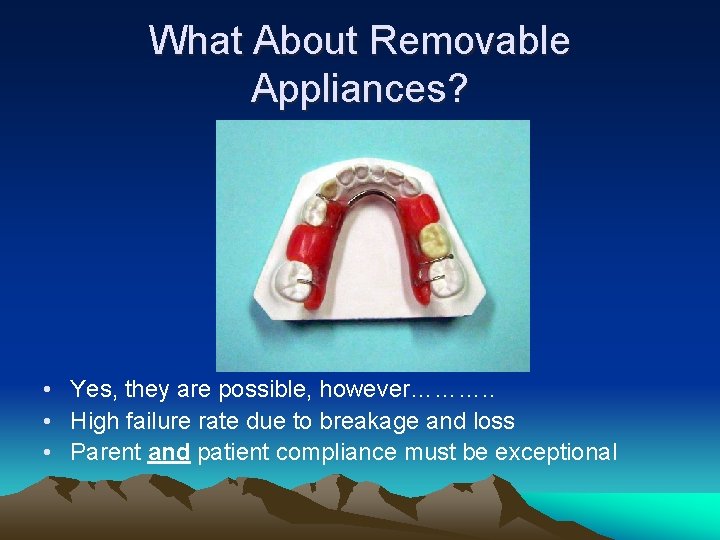

What About Removable Appliances? • Yes, they are possible, however………. . • High failure rate due to breakage and loss • Parent and patient compliance must be exceptional